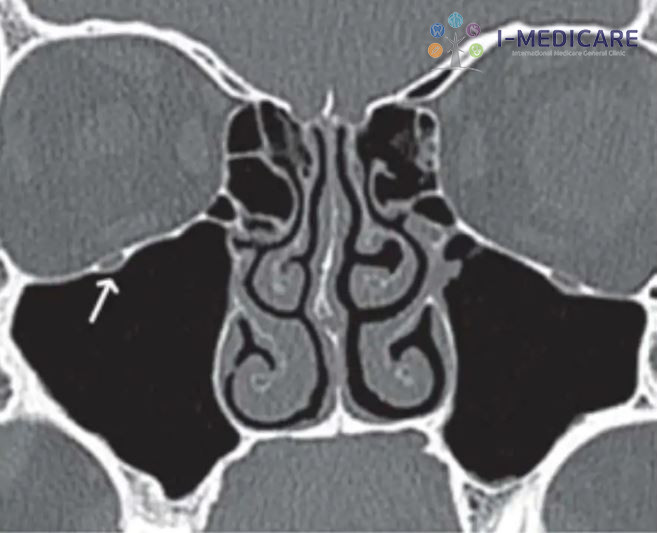

Khi nào cần đến bác sĩ và can thiệp chuyên khoa

Nếu các triệu chứng không cải thiện sau khoảng 10 ngày điều trị tại nhà, hoặc xuất hiện dấu hiệu nặng như sốt cao, đau đầu dữ dội, sưng quanh mắt hay giảm thị lực, người bệnh cần đi khám ngay. Lúc này, bác sĩ tai mũi họng có thể chỉ định chụp CT xoang để đánh giá mức độ viêm, xác định vị trí tắc nghẽn và phát hiện sớm các biến chứng.

Trong những trường hợp viêm xoang mạn tính không đáp ứng với điều trị nội khoa, phẫu thuật nội soi xoang có thể được cân nhắc nhằm mở rộng lỗ thông xoang, loại bỏ polyp hoặc chỉnh sửa các bất thường cấu trúc. Phương pháp nội soi hiện nay ít xâm lấn, thời gian hồi phục nhanh và mang lại hiệu quả cao cho người bệnh.